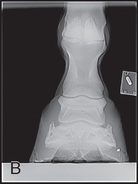

Digit/foot: P-III (distal phalanx, coffin bone) P-II (middle phalanx) P-I (proximal phalanx-pastern) Proximal interphalangeal joint (pastern joint) joint | DP (Standard) (Fig. 24.62B,C) | Dorsal 45-degree proximal–palmarodistal (D45Pr-PaDi) | Foot slightly forward on image receptor. | Perpendicular to foot axis at MSP (midsagittal plane) at area of interest with beam angled ~45 degrees to ground |

| Lateral (Standard) (Fig. 24.62D) | Lateromedial | On a block to elevate limb for P-III; resting on ground for other views. | 90 degrees lateral to MSP, parallel to ground on area of interest: coronary band for PIII | |